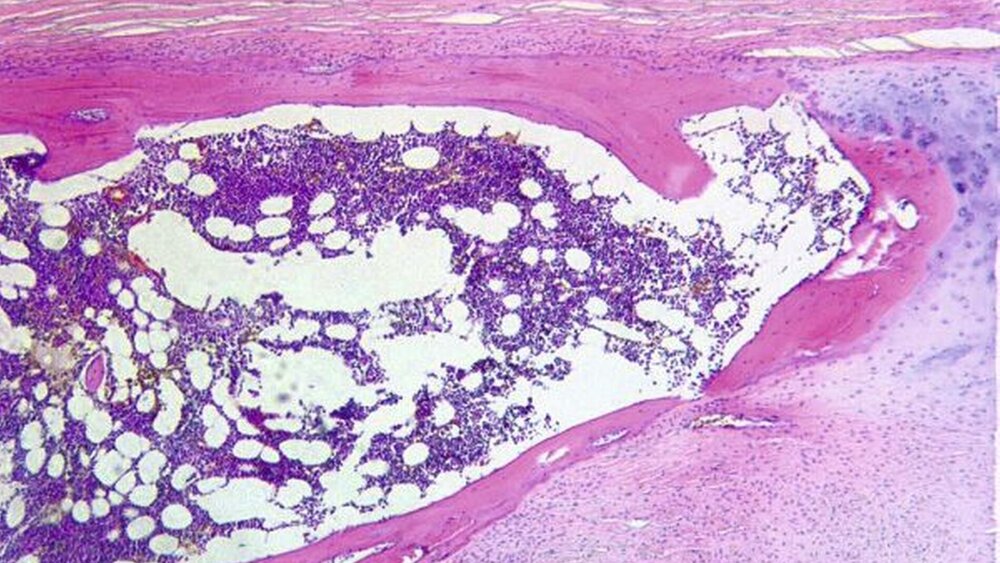

Mit dem Verdacht auf das Vorliegen eines Processus Styloideus-Stylohyoideus-Syndroms erfolgte die operative Resektion des Processus styloideus sowie des verknöcherten Ligamentum stylohyoideus beidseits, über einen retromandibulären Zugang in Intubationnarkose (Abbildungen 2 und 3). Der histologische Befund der Resektate, ergab Ligamentanteile mit metaplastischer Knorpel- und Knochenneubildung (Abbildung 4).